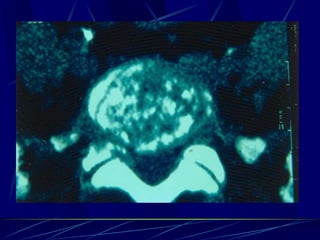

Echinococcus